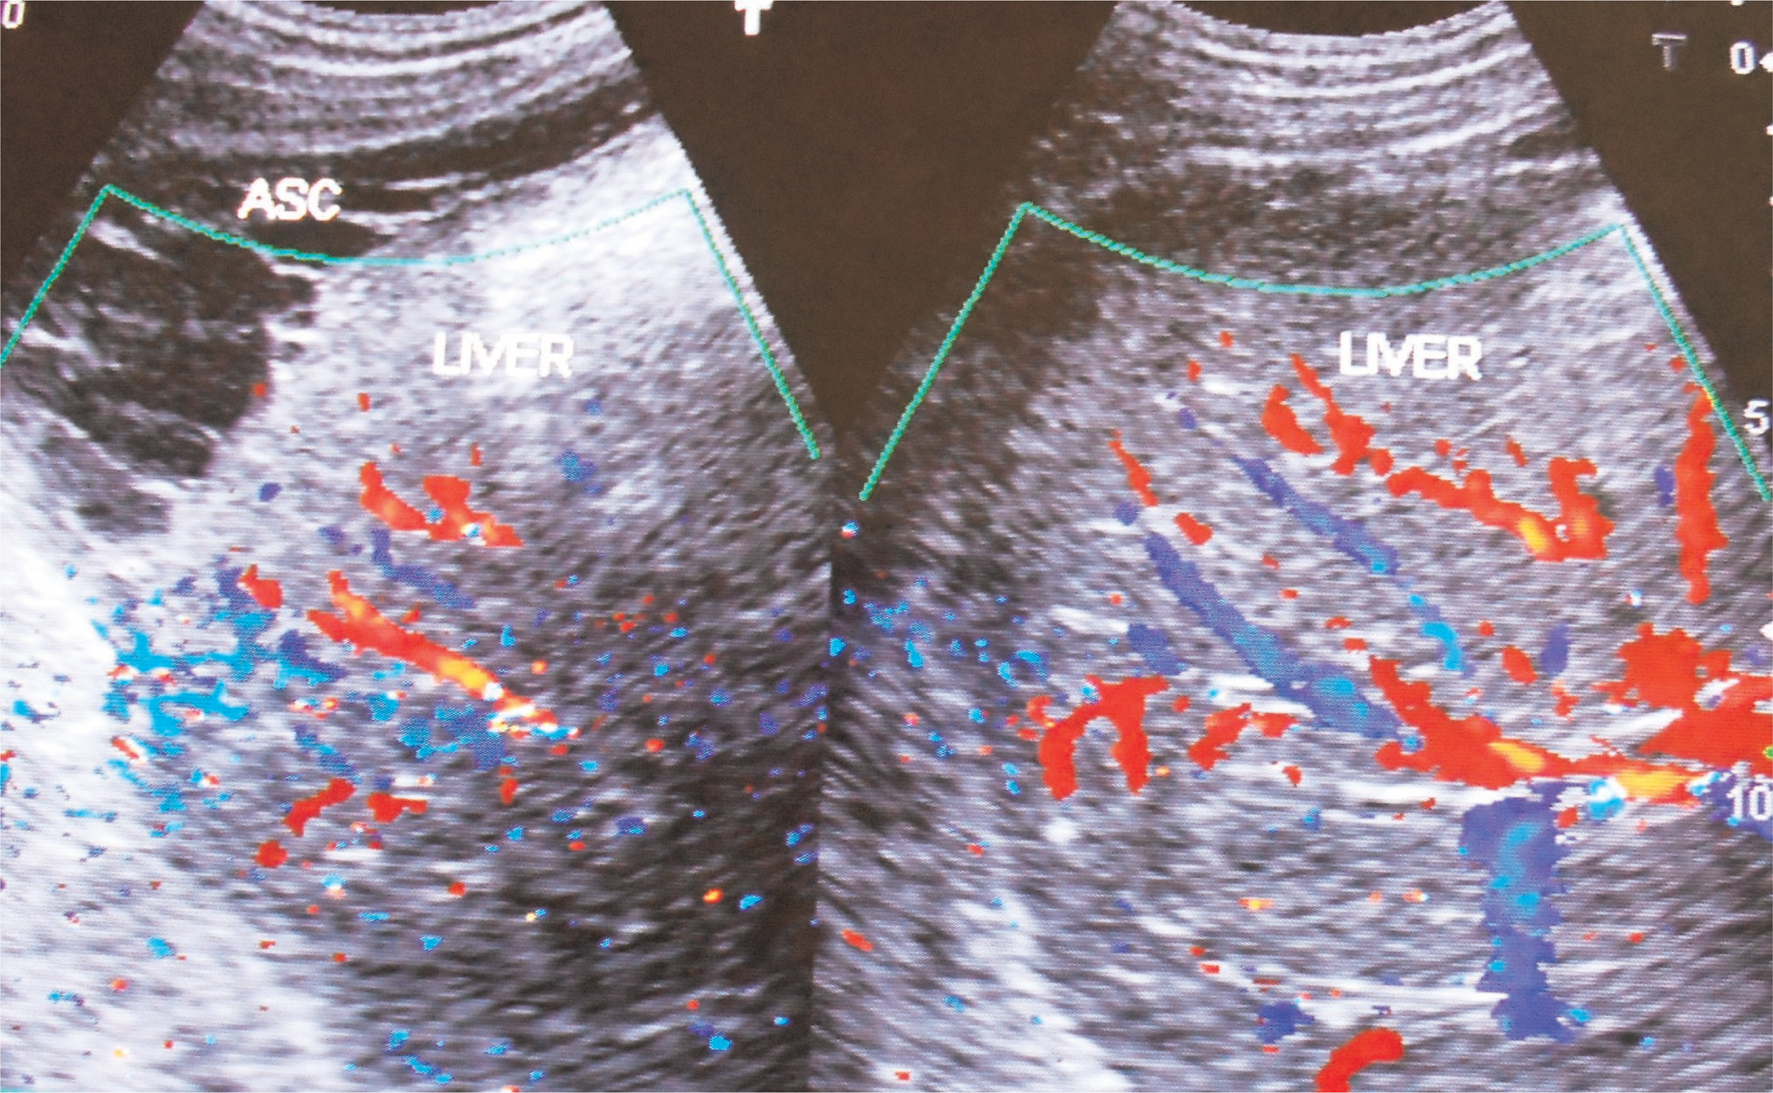

HVCS develops in any age group of either sex. Ascites in HVCS is common in persons with poor nutrition or history of alcohol abuse, in whom it is usually precipitated by bacterial infection like puerperal sepsis, chronic diarrhea, and fever or by surgery. Even infants on parenteral nutrition develop this condition. Dilated superficial veins in abdomen with upward blood flow are observed (Figure 4). US/CD examination is diagnostic (75). It shows hepatomegaly and ascites often with evidence of bacterial peritonitis, free-floating particles that settle on standing, acute peritonitis and thick peritoneum with adhesions, loculations, or evidence of perihepatitis indicating chronic peritonitis (Figure 5). Segmental stenosis of medium-sized intra-HVs and prominent main HVs with obstruction to blood flow at the HV outlets will be demonstrated in US/CD. IVC at the site of HV outlet shows stenosis with thick posterior wall with recent and old organized thrombi of different ages along its posterior wall (Figure 6). Gallbladder wall is thick and edematous. Neutrophil leukocytosis or left shift and high level of CRP are common at the onset. Bedside inoculations of blood and ascitic fluid in aerobic blood culture bottle during the initial visit are likely to yield positive culture. Hypersplenism is common in patients with HVCS. Such patients presenting with acute ascites may have normal or slightly elevated WBC count but low platelet count. Levels of serum bilirubin, alanine, and aspartate aminotransferase will be elevated. Cavogram and liver biopsy are not necessary for diagnosis. HVCS patient without ascites usually have normal levels of bilirubin, alanine, and aspartate aminotransferase, but US/CD examination shows IVC with localized stenosis with thick echoic posterior wall in at the level of HV outlet and old organized thrombi along the posterior wall of the distal dilated segment.

Fig 5

Figure 5. Ultrasonography and color Doppler of a patient with HVCS showing ascites with evidence of chronic peritonitis—Multiple intraperitoneal adhesions. Note the thrombosed, medium-sized branches of portal veins. ASC, ascites. (Copyright: Santosh Man Shrestha).